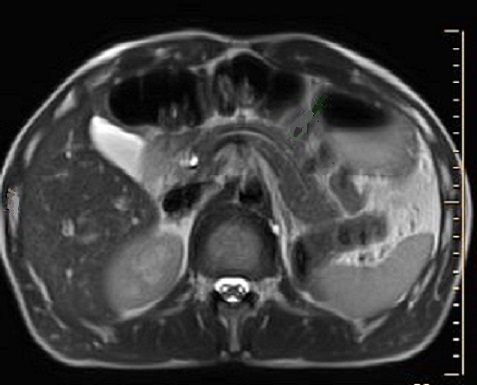

Image IRM normale

du pancreas

: L'aspect IRM du pancreas depend du degre de

l'infiltration graisseuse du parenchyme de pancreas

.. Sur les sequences ponderee T1 avec saturation de

graisse le pancreas prene

un signal igentique ou legerement inferieure a celui

du foie . Sur le pancreas a infiltration graisseuse

, il apparait hypersignal . Dans les coupe

ponderee T2 le signal du pancreas est identique a

celui du foie . L'infiltration geraisseuse du

pancreas se trtaduit par un diminution du singal T2

( hyposignal ) |

Sur coupe axiale IRM

ponderee T1 le pancreas se present sous forme une

crochet avant aort et le tronc coeliaque , a bord lisse ,

regulier avec signal isointense que le foie . |

Image IRM du pancreas normale , coupe

axiale ponderee sur T2 , le pancreas est hypointense

et identique que le foie |